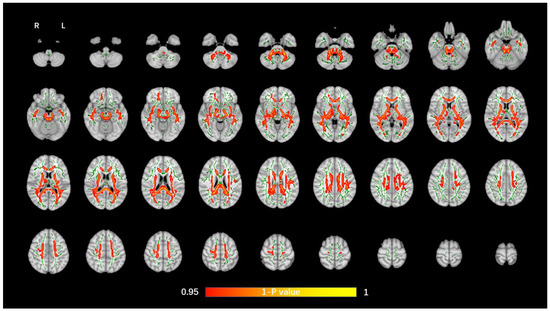

The average FA WM skeleton of all subjects was constructed in TBSS analyses, as shown by the green line in Figure 1, Figure 2, Figure 3 and Figure 4. An analysis of variance of voxel level was carried out on the WM skeleton, and the differences among the three groups were compared. p < 0.05 after FWE correction based on TFCE was statistically significant. Statistically significant areas were expanded to better show the position of WM fiber bundles, as shown in the red part in Figure 1, Figure 2, Figure 3 and Figure 4. The statistical results showed that the DTI indexes of most fiber bundles were statistically significant. There was a significant statistical difference in the FA, MD, AD, and RD values of the FMI, FMA, IFOF, SLF, ILF, ATR and corticospinal tract (CCT) among the three groups (p < 0.05; Figure 1, Figure 2, Figure 3 and Figure 4).

Figure 4.

Voxel-wise TBSS analysis results of RD images among the WML-VCIND, WML-VaD, and HC groups. Green represents the mean WM skeleton of all subjects. Red-yellow (thickened for better visibility) represents regions with a significant F-test statistical difference (p < 0.05, TFCE-based FWE-corrected). TBSS, tract-based spatial statistics; RD, radial diffusivity.